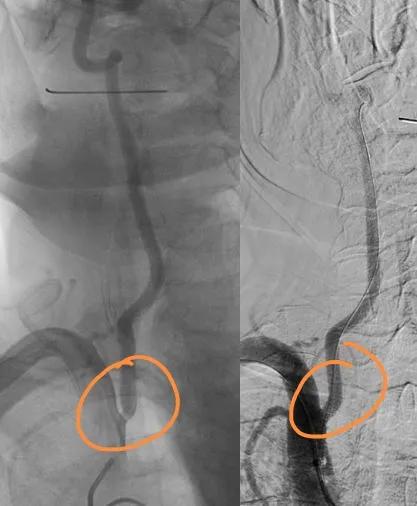

经过和家属沟通交流,施行了局部麻醉下微创介入支架手术,放入了一枚药物涂层球扩支架

大家看最后效果:

支架前后对比